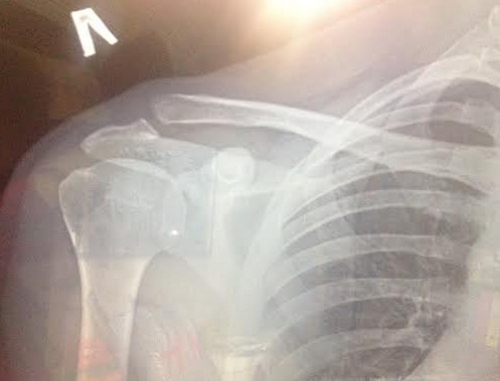

При травмах третьей степени повреждаются ключично-клювовидная и ключично-акромиальная связки. Это состояние сопровождается болевыми ощущениями в области плеча и ограничением подвижности руки. На рентгене наблюдается значительное увеличение межсуставного расстояния и смещение ключицы относительно акромиона.

Для точного определения степени и давности травмы анализируются диагностические признаки, такие как расстояние между ключицей и лопаткой на рентгеновском снимке, а также наличие расширения суставной щели.

При травмах первой степени наблюдается незначительное смещение частей акромиально-ключичного сочленения. Эти повреждения не влияют на состояние клювовидно-ключичной связки. Рентгенография выполняется в положении стоя, часто с отягощениями: пациент держит в каждой руке предметы весом около 5 кг. Исследование проводится в нескольких проекциях, а диагноз подтверждается с помощью УЗИ.

При травмах второй степени фиксируется расширение клювовидно-ключичного пространства на 25%. В случае более серьезных повреждений этот показатель может достигать 100%.

Для выявления травм четвертой степени применяется аксиальная рентгенография. Под воздействием провоцирующего фактора ключица смещается назад, захватываемая трапециевидной мышцей. Наиболее тяжелые повреждения сопровождаются разрывом дельтовидной фасции, и клювовидно-ключичное расстояние увеличивается более чем на 200%.

Через 1–3 дня в области поврежденного сустава появляется подкожная гематома. Сильная боль в большой грудной мышце может сопровождать разрыв ключично-клювовидных связок. Окончательный диагноз устанавливается на основе рентгенологического исследования. При полном вывихе наблюдается расхождение суставных поверхностей и увеличение расстояния между клювовидным и ключичным отростками. Для сравнения также исследуется здоровый сустав. МРТ помогает выявить разрывы мягких тканей, окружающих сустав.